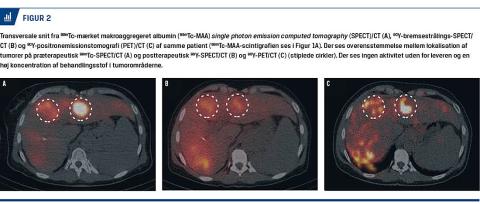

På SPECT/CT vurderes fordelingen af 99mTc-MAA i leveren [7] (Figur 2A). Den tredimensionale fremstilling er særlig vigtig ved vurdering af evt. utilsigtet ekstrahepatisk aktivitet fra 99mTc-MAA. Findes der ekstrahepatisk 99mTc-MAA-aktivitet i ventrikel eller duodenum, kan patienten ikke behandles, før det ansvarlige blodkar er identificeret og emboliseret ved en fornyet udredningsprocedure. Ekstrahepatisk 90Y-aktivitet i ventriklen eller duodenum kan medføre gastritis eller duodenitis [4, 8, 9] og i sjældne tilfælde stråleinduceret ulceration. Derimod er aktivitet i galdeblærevæggen ikke kontraindicerende, da galdeblæren er relativt

stråleresistent.

Modsat andre anvendte isotoper udsender 90Y ikke gammastråling. Der er alligevel mulighed for billeddannelse med gammakamera (eller SPECT) på baggrund af såkaldt bremsestråling. De resulterende billeder er mere uskarpe end ved gammaemitterende isotoper, men af tilstrækkelig kvalitet til at man kan vurdere, om der er behandlingsstof uden for leveren (Figur 2B). Yderligere er der mulighed for at foretage positronemissionstomografi (PET) på baggrund af en meget lille andel udsendte positroner [10]. I leveren, hvor koncentrationen af 90Y er højest, kan man opnå billeder, som har god rumlig opløsning og er kvantitativt korrekte [11, 12] til vurdering af partikelfordelingen og potentielt beregning af den faktisk afsatte stråledosis [13] (Figur 2C).